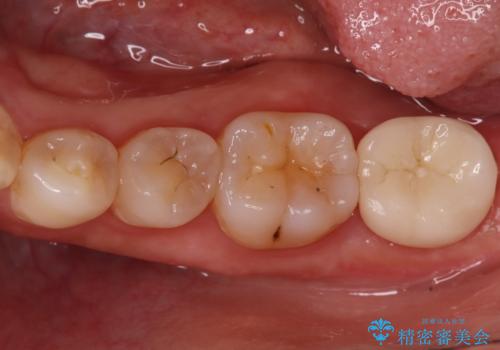

歯と歯の間の虫歯もセラミックで再発防止

担当医 河口智英